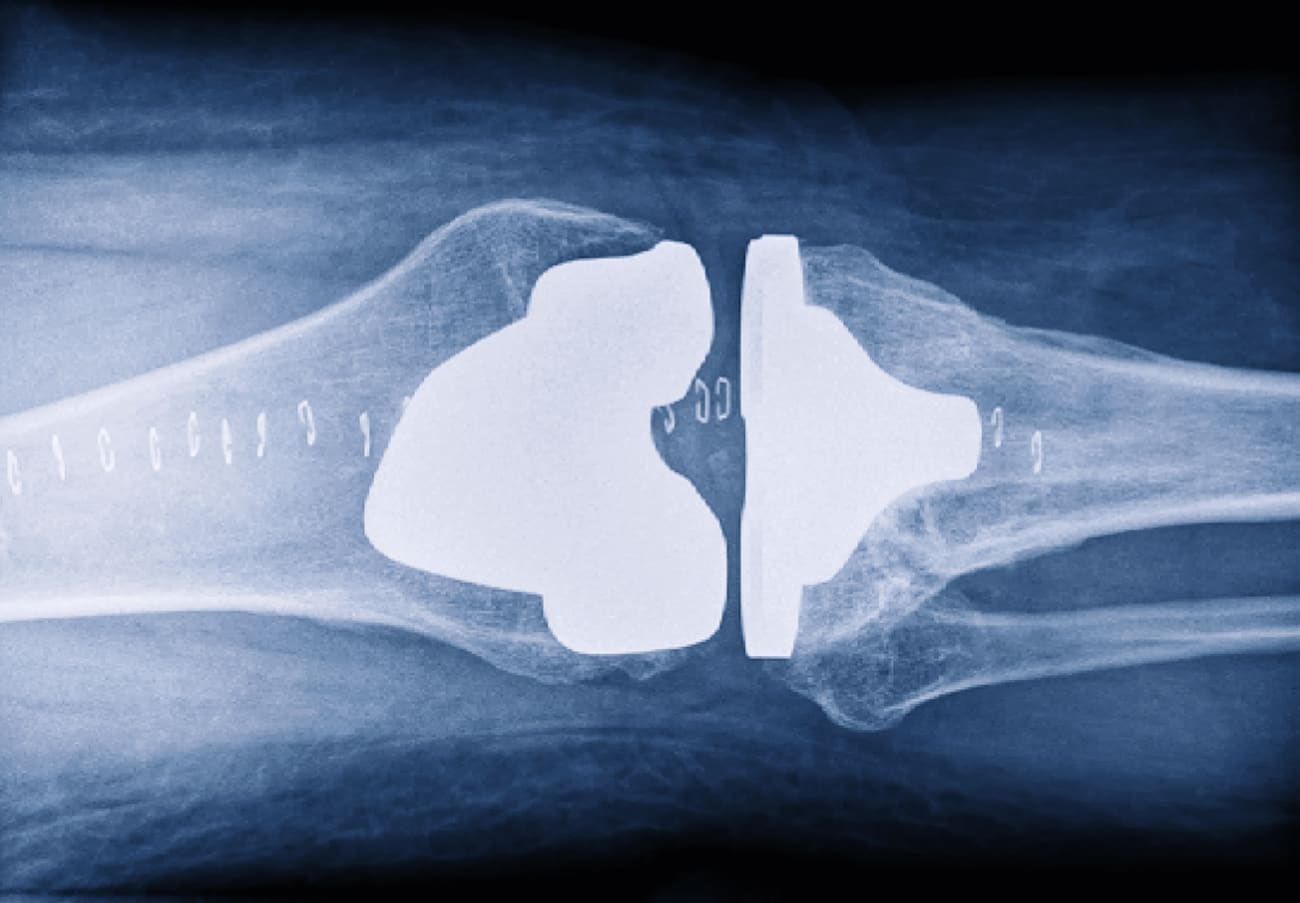

From www.osmifw.com

kneereplacementxray The Orthopedic & Sports Medicine Institute in Nickel-Free Knee Replacement Lawrie’s surprise, no study to date had quantified the metal content in knee replacements performed with “nickel free” implants and. The role of metal allergy, including nickel, in problems occurring with knee replacements and other metal prostheses is a constantly evolving. A comparison of clinical outcomes after total knee arthroplasty in patients with preoperative nickel allergy receiving cobalt. Nickel-Free Knee Replacement.